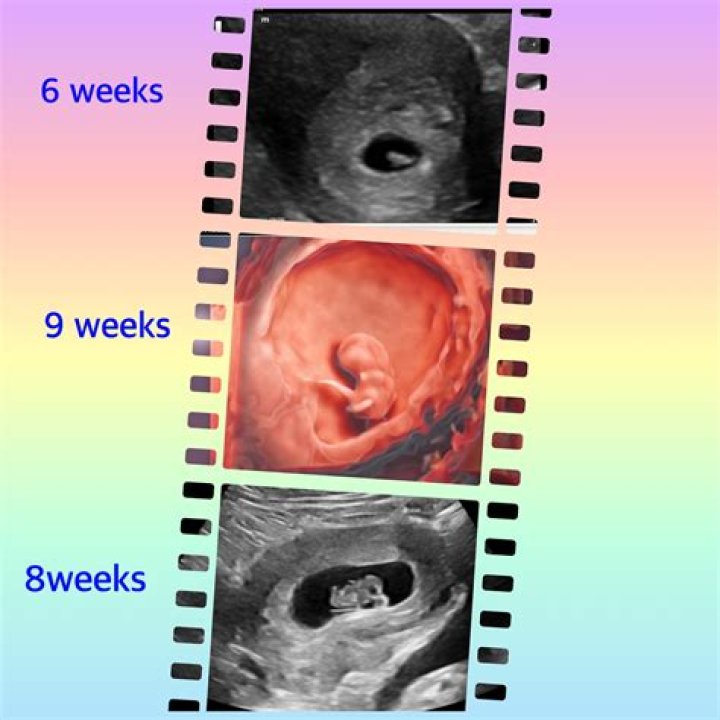

Most practitioners wait until at least 6 weeks to perform the first pregnancy ultrasound. However, a gestational sac can be seen as early as 4 1/2 weeks after your last period, and a fetal heartbeat can be detected at 5 to 6 weeks (though that isn't always the case).

The earliest an ultrasound scan can identify a healthy pregnancy inside the uterine cavity is 17 days after the egg was released from the ovary (ovulation). This is approximately three days after a missed period.

You normally don't have your first ultrasound until at least week 6, but you might be able to spot the gestational sac as early as halfway through week 4 — and if you're having twins, you'll likely see two of them!

At 5 weeks into pregnancy things are so small there is very little to see on ultrasound. Even at 6 weeks it can be difficult to see an embryo with some people.